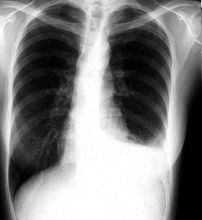

一、胸部X線檢查:本項檢查是發現肺癌的最重要的一種方法。

X線檢查這是診斷肺癌的一個重要手段。大多數肺癌可以經胸部x線攝片和CT檢查獲得臨床診斷。中心型肺癌早期X線胸片可無異常徵象。當癌腫阻塞支氣管,排痰不暢,遠端肺組織發生感染,受累的肺段或肺葉出現肺炎徵象。若支氣管管腔被癌腫完全阻塞,可產生相應的肺葉或一側全肺不張。當癌腫發展到―定大小,可出現肺門陰影,由於腫塊陰影常被縱隔組織影所掩蓋,需作胸部X線斷層攝影和CT檢查才能顯示清楚。